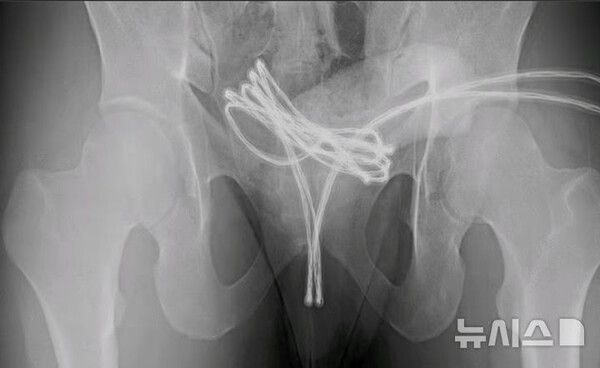

미국의 한 대학생이 요도에 USB 케이블을 넣었다가 응급 수술을 받는 사건이 발생했다.

뉴시스 보도에 따르면, 12일(현지시각) 영국 매체 데일리메일에 따르면 미국의 한 대학생이 성적 쾌감을 위해 요도에 USB 케이블을 삽입했다가 응급실로 실려 갔다.

검사 결과 그는 고리 모양의 케이블을 요도로 깊숙이 밀어 넣어 방광으로 들어간 뒤 끼어 버린 것으로 나타났다.

의료진은 "처음에 직원들이 손으로 케이블을 잡아 당기려고 했지만 실패했다"며 "마취를 시키고 요도에 특수도구를 삽입해 케이블을 빼낼 수 있었다"라고 말했다.